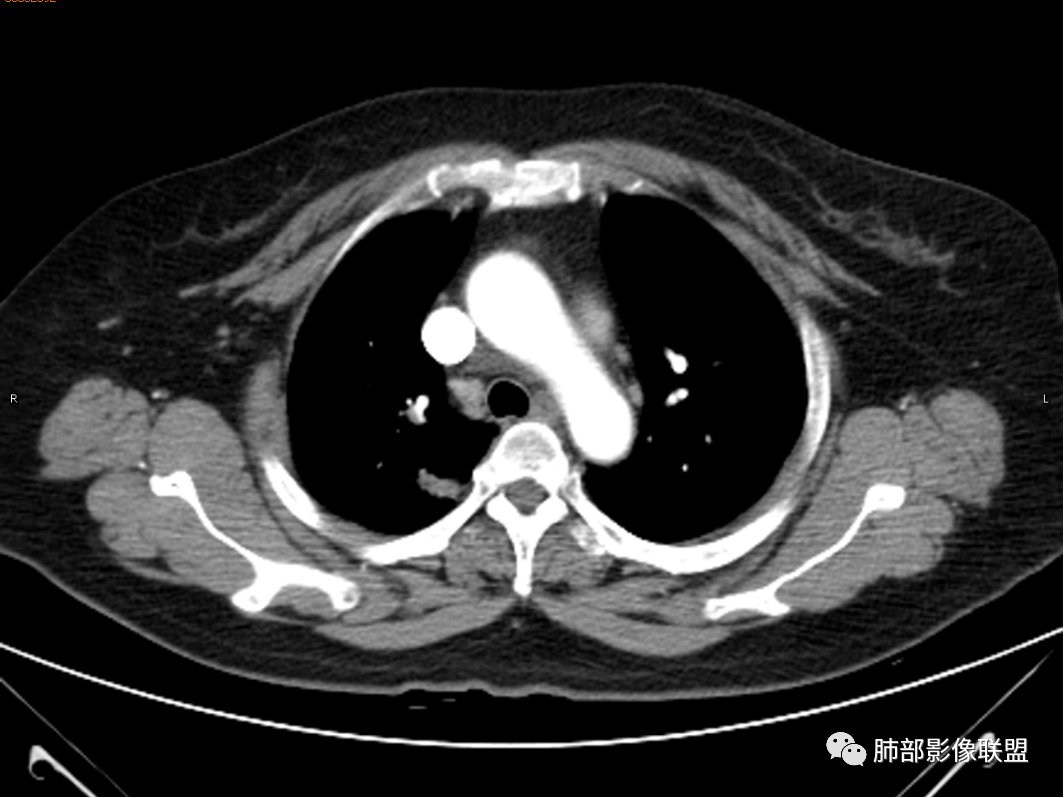

杨丽:老年女性,无肺气肿背景。右肺上叶后段胸膜下肿块,局部浅分叶,边缘见长软毛刺,支气管通入,临近叶间胸膜略增厚,增强扫描可见明显坏死,坏死边界清晰,壁较薄,其余病灶中等强化。纵隔小淋巴结。考虑:感染性病变,结核?鉴别囊肿伴感染。

穿越七海的风:女性,右肺上叶肺内类圆形肿物,部分边缘平直,环行强化明显,周围磨玻璃考虑出血,结核鉴别类癌。

寒江雪:椭圆形肿块,局部紧贴胸膜,软毛刺,纵隔淋巴结。强化壁薄、均匀。考虑炎性病变,结核?囊肿伴感染待排。

杨泽锋:病灶不大,坏死彻底,尽管卫星灶树芽征不明显(可能层厚太厚了),还是首先考虑TB

王武章:较为符合淋巴结结核破溃肺内浸润,主要与支气管囊肿(并感染?)鉴别

红星:咳嗽咳痰,痰中带血一个月。右肺上叶后段一个结节的阴影,分叶毛刺,肺门有淋巴结的肿大,CT值是软组织的密度。增强扫描中等程度的强化,见薄环状强化,病灶周围没有卫星病灶。首先考虑结核性的肉芽肿病变。鉴别诊断腺癌、结节病、淋巴瘤。

玫:咳嗽,咳痰,痰中带血一个月,肿瘤标志物不高,右肺上叶肿块影,边界清晰,浅分叶及少许毛刺,增强扫描病灶边缘呈环形强化,病灶内见坏死区,考虑结核可能,鉴别腺癌。

蕊:环形强化,中心性坏死,坏死界线较清楚,肺门淋巴结肿大,考虑结核可能。

薏米:咳嗽,咳痰带血就诊,右肺上叶不规则密度增高影,未见支气管截断,边缘以凹陷收缩为主,环形强化,坏死边界清,坏死比较彻底,考虑结核,鉴别鳞癌、类癌。

青藤之凉:环形强化,中心性坏死,坏死界线较清楚,肺门淋巴结肿大,考虑炎性病变,结核可能,鉴别肺癌。

王秀仙:右肺上叶后段结节,分叶,部分边缘平直部分膨隆,周围可见磨玻璃晕,密度不均,中心低密度坏死,增强薄环状强化,坏死界线较清楚,纵膈小淋巴结肿大,考虑肉芽肿性病变,结核。鉴别鳞癌。

三个石头:右肺上叶结节,平直,鹏隆都有,磨玻璃晕边界不清,坏死边界清,肺门淋巴结大。考虑炎性,结核可能。

任广国:左肺上叶后段,不规则团块,边缘有软毛刺,刀切征,增强扫描其内可见圆形坏死区,壁中等强化,纵隔内淋巴结,均匀强化,无坏死。考虑肺脓肿;鉴别:结核;

傅昌瑜:女性,咳嗽咳痰痰中带血1月。血常规、肿瘤标记物正常。CT:右上叶后段类圆形结节,内侧紧贴纵隔,前与右主支气管后壁分界不清。外后部分边缘平直收缩、矢状位可见U型凹陷、桃尖征,周围见边缘模糊的GGO,软毛刺。右上叶后段支气管似乎变狭窄。增强呈薄壁环形强化,内部强化不明显,强化时边缘似见有多个小结节与主病灶融合(芋艿子?)。远端见细小结节。整体考虑炎性病变,结核可能性大,注意鉴别腺癌。

1.女性,咳嗽咳痰痰中带血1月。血常规、肿瘤标记物正常。             2.CT示右肺上叶不规则肿块,边缘以平直收缩为主,可见U型凹陷及桃尖征,周围见边缘模糊的GGO,软毛刺,从形态学的角度病灶更支持炎性改变; 3.增强呈薄壁环形强化,壁光整、清楚,也支持炎性改变;病灶内部平扫CT值密度比较高,约40HU,明显高于水的密度,而且未见强化,提示病灶的坏死可能为凝固性坏死;    4.从上面的分析,病变更符合炎性,患者白细胞不高,治疗后没有好转,不支持普通细菌的感染;影像病灶较局限,边界较清楚,病灶慢性炎症或肉芽肿,形态机发病部位更符合继发性肺结核。患者非易感人群,病灶孤立,尽管有液化,也很难第一时间考虑真菌,尤其是曲霉菌感染。什么是炎性肉芽肿?炎性肉芽肿的常见疾病谱系有哪些?那什么是凝固性坏死和干酪样坏死?跟一般的液化性坏死有什么区别?接下来我们逐一学习一下。